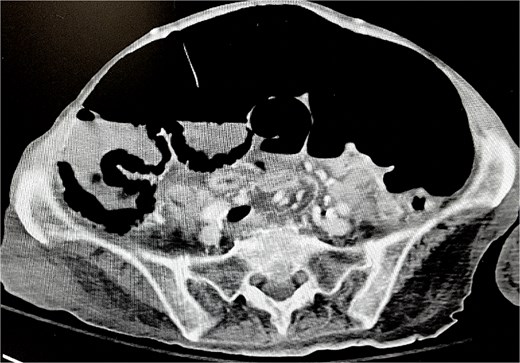

Despite aggressive respiratory support, her clinical course necessitated prolonged intubation and eventual tracheostomy placement. During her ICU stay, she developed progressive abdominal distension. Imaging revealed colonic ileus, with concern for distal obstruction. Gastroenterology administered neostigmine on two occasions without clinical improvement. Worsening abdominal distension and exam findings prompted further imaging, which demonstrated cecal pneumatosis with suspicion of ischemia (Fig. 1).

Development of cecal pneumatosis after administration of neostigmine.